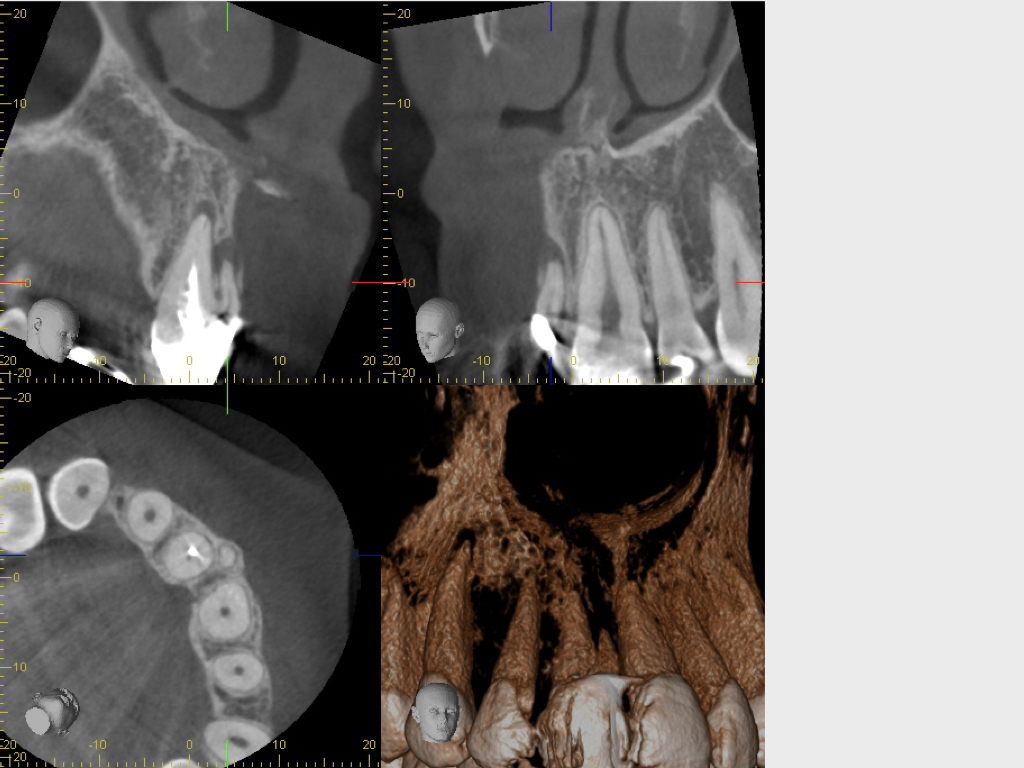

8887.005

Latente Beschwerden seit Jahren (2).